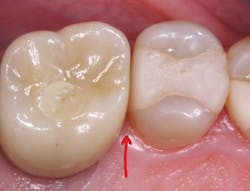

Hard and wear-resistant crown materials (figure 2) Restorative dentists dislike cutting off zirconia or lithium disilicate crowns because of their hardness and difficulty to cut. Do these two popular materials wear at a similar rate as tooth enamel? Clinicians Report Foundation’s research has shown that unglazed and unstained 3Y full-strength zirconia and lithium disilicate wear at the same rate as enamel (figure 3). However, when stain and glaze are placed on either material to produce better esthetics, the crowns wear the opposing teeth significantly. Almost all zirconia crowns of all iterations and lithium disilicate have stain and glaze placed on them. Other than 3Y full-strength zirconia, almost all other varieties of zirconia studied in vivo to date wear opposing enamel—glazed or not.1

Although porcelain-fused-to--metal (PFM) crowns also wear opposing enamel, the nearly total indirect restoration use of zirconia and lithium disilicate crowns causes varying degrees of wear, further contributing to changes in occlusion.